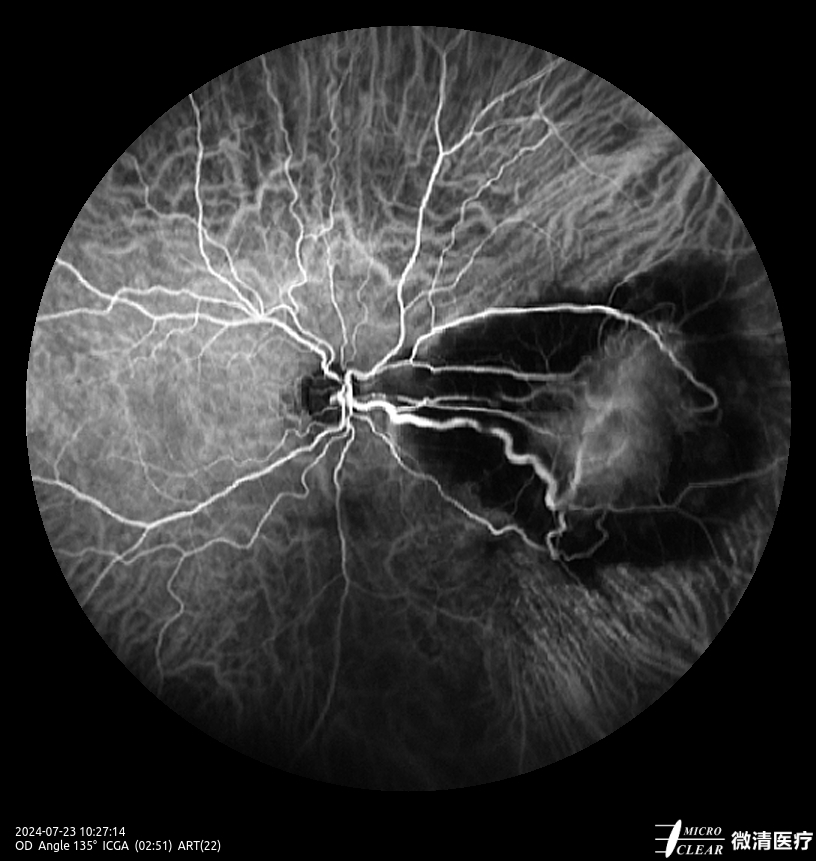

- Fundusfluoresceïne-angiografie (FFA)

- 135° WA (Groothoekangiografie) – in één opname

Confocale Scanning Laser Oftalmoscoop (CSLO)

- Combinatie van drie confocale laserbronnen voor maximaal contrast en getrouwheid.

- Verbeterd confocaal ontwerp zorgt voor een betere scheiding van de netvlieslagen en verbeterde penetratie door cataract en oculaire troebelingen.